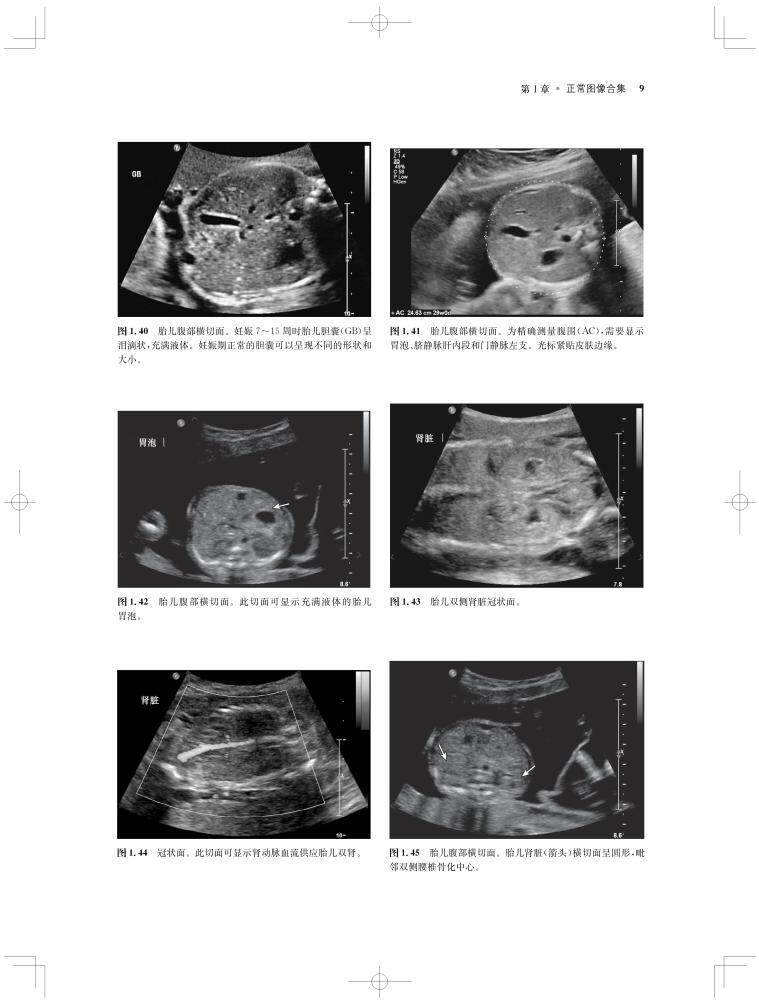

内容涵盖了胎儿宫内疾病的所有病种,从疾病的概述、流行病学、病因学、病理生理学,到临床表现、各类影像学技术的诊断和鉴别诊断,再到产前、产后的治疗和干预手段,都做了全面介绍,重点阐述了疾病的超声、X线、CT、MRI、PET、CT等影像学表现,以及诊断与鉴别诊断,并辅以大量标准化的影像学图片,图文并茂。

《产科影像学——胎儿诊断和监护》是Elsevier(Saunders)出版的“Expert Series”之一,由国际最顶尖的妇产科、生殖科、母胎医学和影像学专家共同编写,代表着该领域最顶尖的水平。书中配有大量典型影像图片,内容丰富全面,编写理念先进,侧重于疾病的影像学征象分析及鉴别诊断和诊断流程的制定,从临床思维上进行了更新;同时兼顾临床和病理医师,重点内容以列表、提要、要点的形式进行总结,提纲挈领,方便读者阅读、记忆。对于每天不断进行诊断与鉴别胎儿疾病的影像工作者、病理科和临床医师而言,具有重要的参考价值。